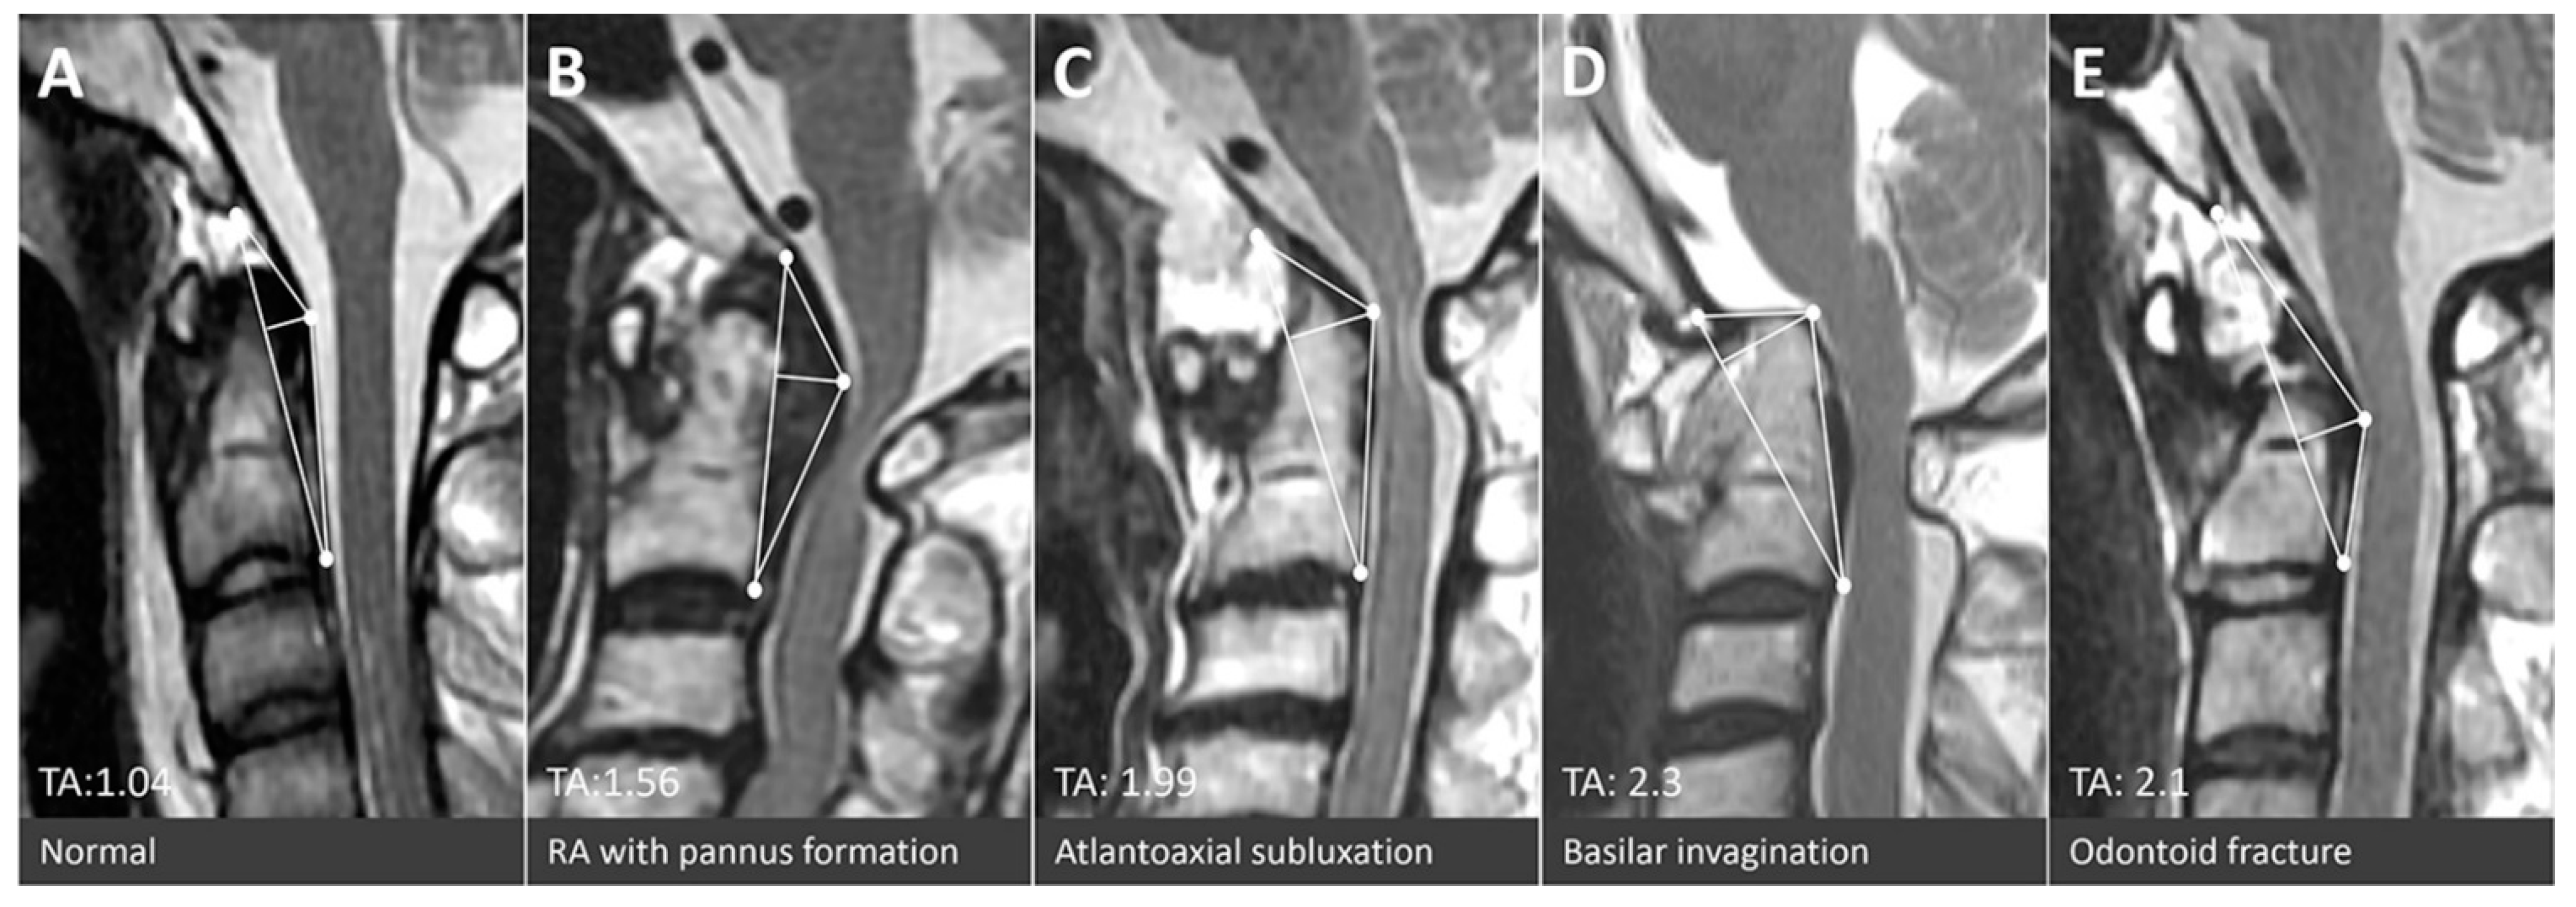

| Triangular area (cm2) | 1.05 ± 0.26 | 0.96 ± 0.31 | 1.58 ± 0.47 | <0.001 | |||

| pathology | Atlantoaxial subluxation | Basilar invagination | Odontoid fracture | Os odontoideum | |||

| n | 90 | 3 | 31 | 5 | |||

| Triangular area (cm2) | 1.54 ± 0.42 †,‡ | 1.84 ± 027 †,‡ | 1.62 ± 0.56 †,‡ | 2.15 ± 0.62 †,‡ | |||